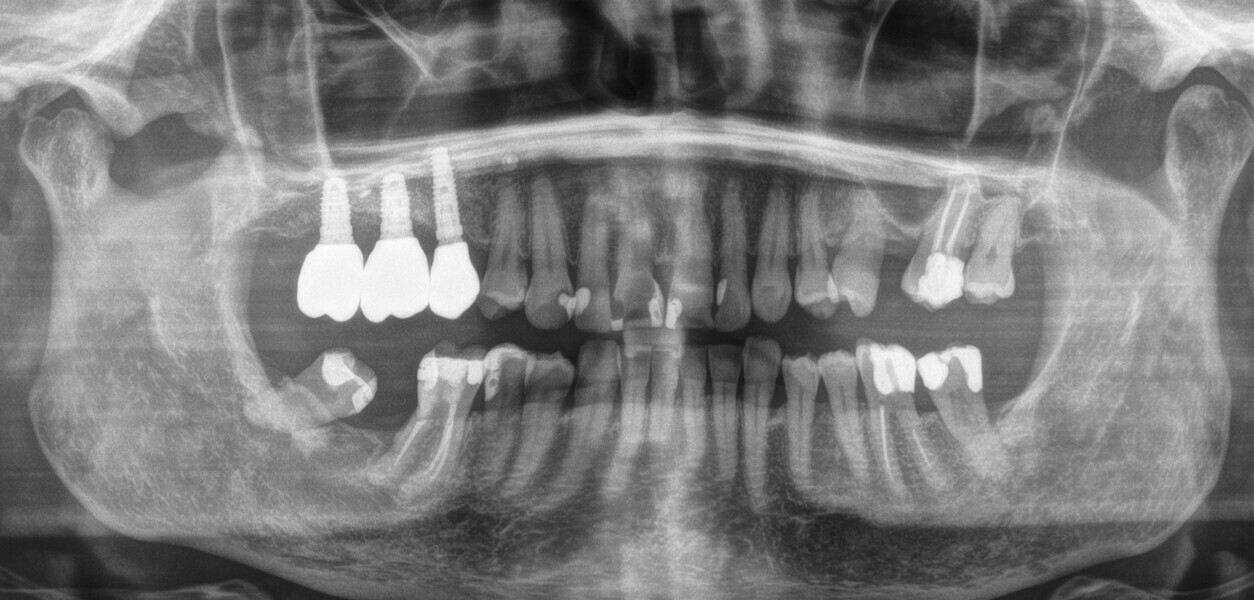

A 62-year-old female patient (ASA Class I), a non-smoker and with normal glucose levels, with previously treated periodontal disease presented for implant and prosthetic rehabilitation of the upper jaw (Fig. 1). Radiographic analysis, performed through a dental panoramic tomogram and CBCT scan, revealed the presence of a vertical bone defect in the right posterior sextant, due to the complete loss of the alveolar process (Figs. 2; 3a & b). The clinical examination showed the severity of the bone defect, which had resulted in an obvious volume deficiency in both the horizontal and vertical dimensions (Figs. 4 & 5).

Subsequently, the surgical guide was placed and fixed in the planned position, the implant sites were prepared with progressive dedicated drills and three conical implants (T3, ZimVie) were placed in sites #15, 16 and 17 according to the prosthetically guided plan obtained from the guided surgery software (Figs. 29, 30a-c, 31a & b). The implants were covered to allow for proper osseointegration, and first intention closure was performed (Figs. 32a & b). After implant placement, a dental panoramic tomogram was taken (Fig. 33).

After three months, the implants were exposed through an apically positioned flap to increase the amount of keratinised tissue on the vestibular side of the implants and to realign the mucogingival junction, previously shifted towards the palate. Flared healing screws were placed to promote proper transmucosal healing. After one month, single ceramic crowns were placed for the first functional loading and temporary restoration while waiting for complete bone maturation (Fig. 34). After six months, the crowns were replaced with zirconia crowns for the final functional loading and the definitive restoration (Figs. 35–38). Clinical and radiographic follow-ups at the first functional loading, at six months, 12 months and 24 months showed the health of the peri-implant tissue and the maintenance of peri-implant bone levels (Figs. 39a-d).